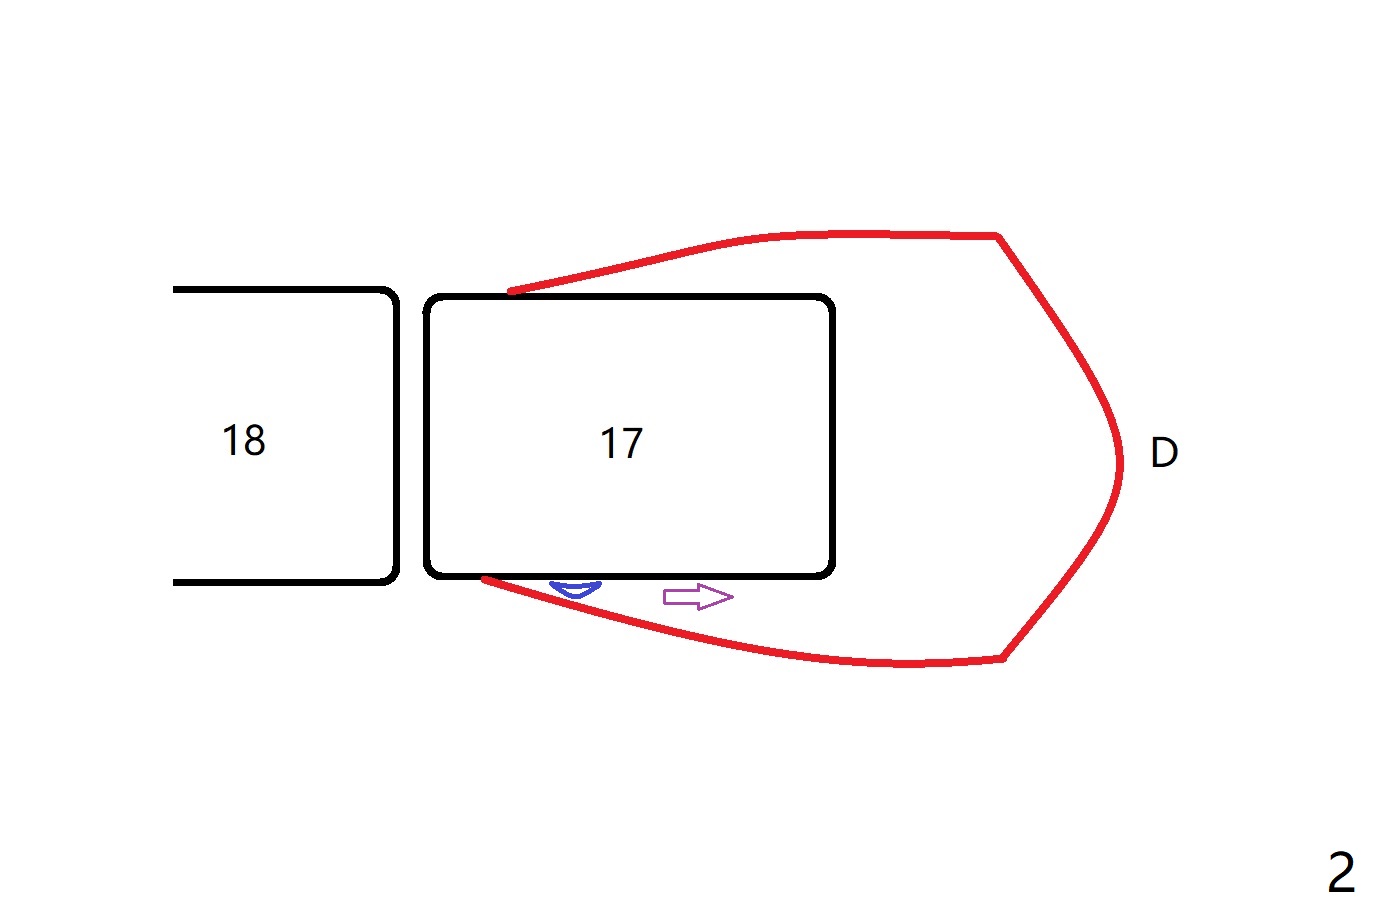

A 20-year-old woman requests extraction of #17 with distal bony defect (Fig.1 *). Since #17 and 18 are close to each other (as compared to the other case), small elevator is not initially inserted between them without incision. The elevator slides distal (Fig.2 (occlusal view)). Incision has to be made for better vision. In spite of block anesthesia, pain is severe. When local anesthetic is being injected into the lingual gingiva, the patient is shivering. As the tooth is removed, a large piece of granulation tissue is attached to the tooth (Fig.3 D (green circle)), while a small piece of granulation tissue remains to the lingual wall of the socket (L (green oval)). After debridement and irrigation, a piece of Osteogen Plug is placed, followed by 5-0 Chromic gut suture.